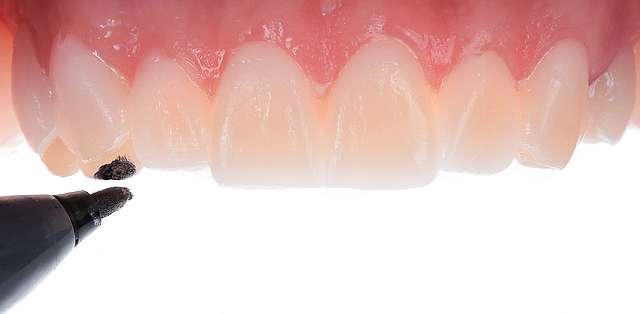

The mock-up just like a treatment plan can simulate a diverse array of procedures that vary on cases basis. In this case, we have dental implants and tissue grafts in posterior areas, on both sides, and ceramic veneers and crown lengthening in anterior side to balance the smile. As a fine detail , you can see how the dentist uses a black marker to simulate the area of the tooth which will be reduced. The mock-up, once accepted becomes a cental pillar in an interdisciplinary treatment. It will be used to determine how the gums will be remodelled , where the implants should be placed, and how the teeth need to be prepped for the future restorations.